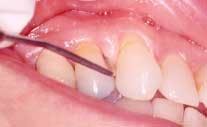

Nicotinic stomatitis, or smoker's palate, is another oral change that is characteristic of smokers. It is characterized by prominent mucous glands with inflammation of the orifices and a diffused erythema, or by a wrinkled, "cobblestone" appearance of the palate often described as a "dried lake bed" effect (See Figure 3). This visual appearance is the result of thickening of the epithelium adjacent to the orifice in response to chronic irritation. The regression of these lesions upon smoking cessation has led many researchers to conclude a cause-and-effect relationship.